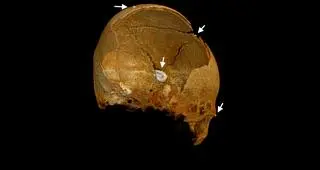

Badanie tomografii komputerowej czaszki

Po analizie uszkodzeń kości biegli chcą ustalić, jak zginęli żołnierze na Westerplatte

W trakcie prac biegli zbadali wszystkie znalezione kości. Stwierdzone zmiany dokładnie opisali i sfotografowali. Biegły radiolog zlecił i wykonał badania tomografii komputerowej wybranych elementów szkieletów, żeby zweryfikować uszkodzenia.

Instytut Pamięci Narodowej w Gdańsku przesłał do mediów również film, na którym zilustrowano wyłamanie około połowy kości pokrywających część mózgową czaszki i większość kości części twarzowej czaszki. Strzałkami i czerwonym kolorem na kolejnych zdjęciach zaznaczone są odłamki metalu wbite w kości czaszki.